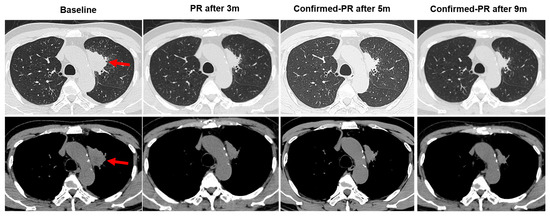

3.1. Case Description